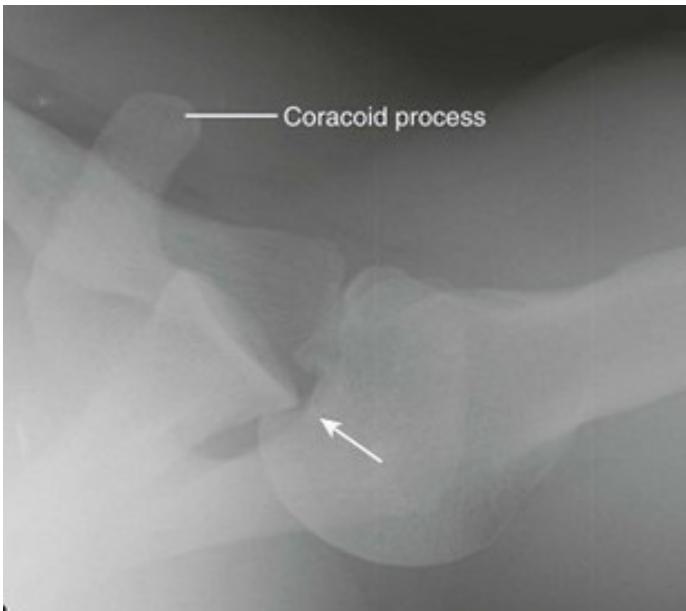

| For Glenohumeral joint: | |

o Feel the coracoid, go lateral to it from anterior![]() ![]() Posterior glenohumeral injection | |